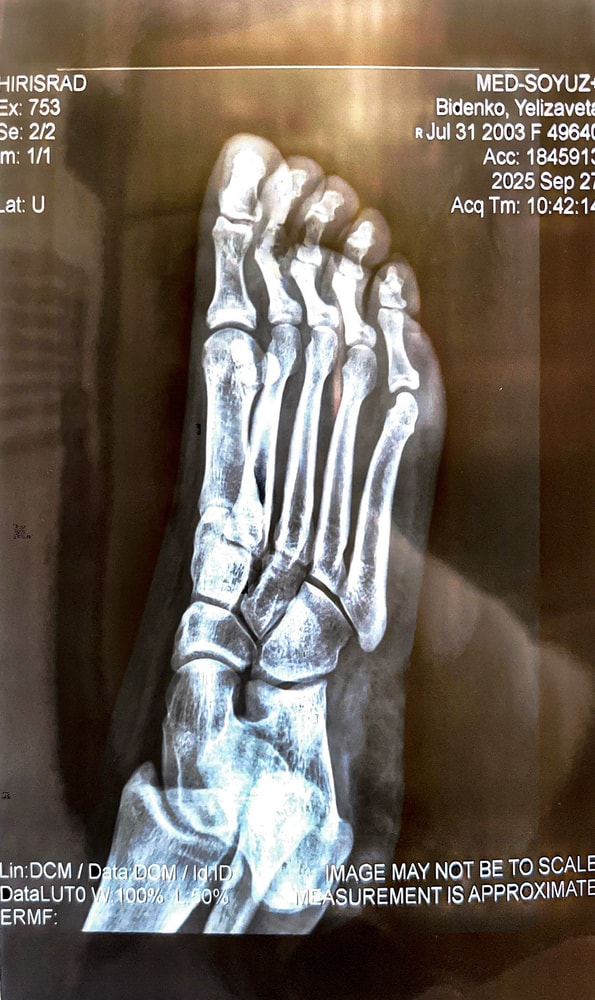

Если ли тут трещина 2,3 палец ?? Очень сильно опухло , гематома ступать больно . А к врачу в понедельник. Травмпункт ужасный